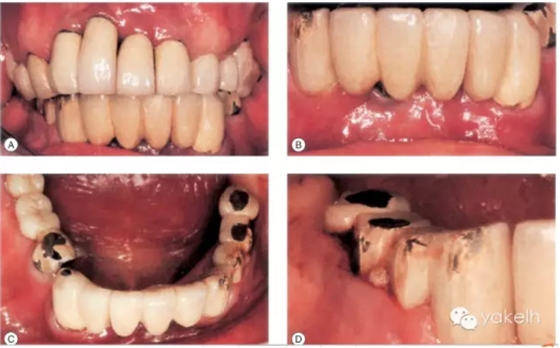

病例9

這個(gè)病例使用種植修復(fù),效果較差。在上頜前牙區(qū),存在嚴(yán)重的美學(xué)問題(圖.12A)。

下頜有一顆種植體位于LR1和LR2之間的外展隙區(qū)域,這不僅影響美觀,同時(shí)也不利于口腔衛(wèi)生的維護(hù)(圖.12B)。

大多數(shù)修復(fù)體都發(fā)生了崩瓷,治療效果不佳(圖.12C)。LR5種植體周圍溢膿,存在種植體周圍炎(圖.12D)。

該病例全頜曲面斷層片顯示(圖.13)種植體修復(fù)存在一系列問題。LR5種植體周圍骨組織完全喪失,LL3發(fā)生了種植體周圍炎,LL6冠與基臺(tái)未完全密合。

圖.12 該病例臨床效果差。多個(gè)修復(fù)體失敗,發(fā)生了種植體周圍炎,還存在美學(xué)問題。

圖13 全頜曲面斷層片進(jìn)一步證實(shí)LR5種植失敗,其他種植體存在種植體周圍炎以及修復(fù)體與基臺(tái)不密合。